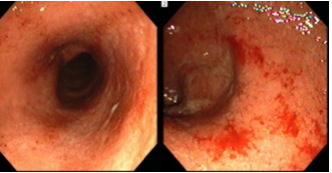

A 56 year old man with a history of chronic liver disease comes to the ER with hematemesis. Based on the specimens below, what is his diagnosis, what caused this anomaly, and how should he be treated?

Esophageal varices= dilatation of submucosal esophageal veins, often due to portal hypertension secondary to cirrhosis

Below: Portal hypertensive gastropathy= increased vascularity of stomach mucosa (milder form of portal HTN pathology)

A 35 year old man complains of new onset pain with swallowing. He is sexually active and states that he recently engaged in unprotected oral sex with another man. Based on the endoscopic view below, what is his diagnosis?

Herpes esophagitis: pain with swallowing (odynophagia) due to severe inflammatory process disrupting esophageal mucosa

Histo: lateral margin of ulcer: see Cowdry A intranuclear inclusions